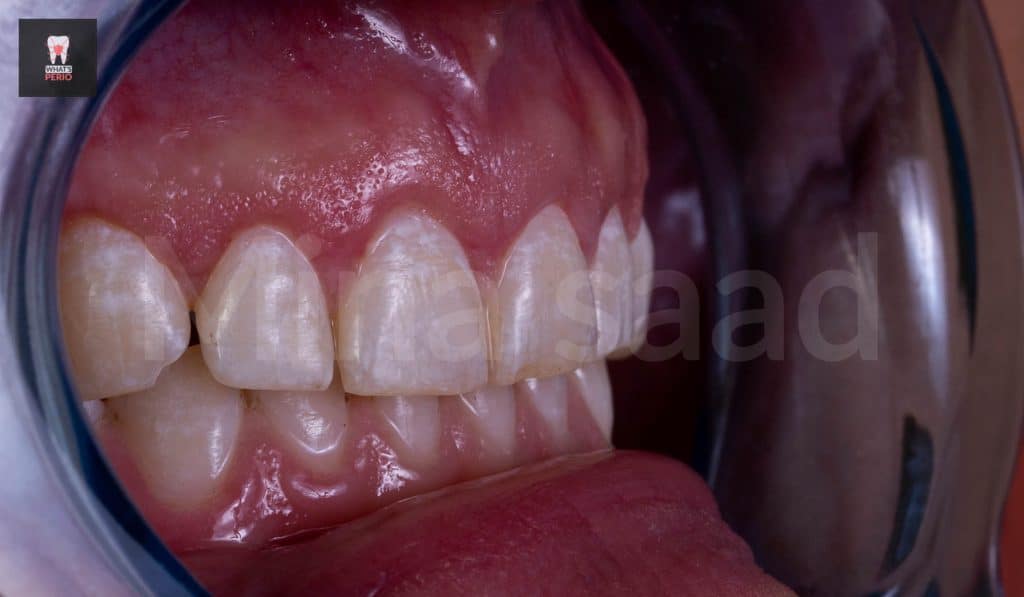

-The patient is recalled after 4 weeks & it was observed that the gummy smile was decreased & the patient was very satisfied with the result & decided to postpone the 2nd step.